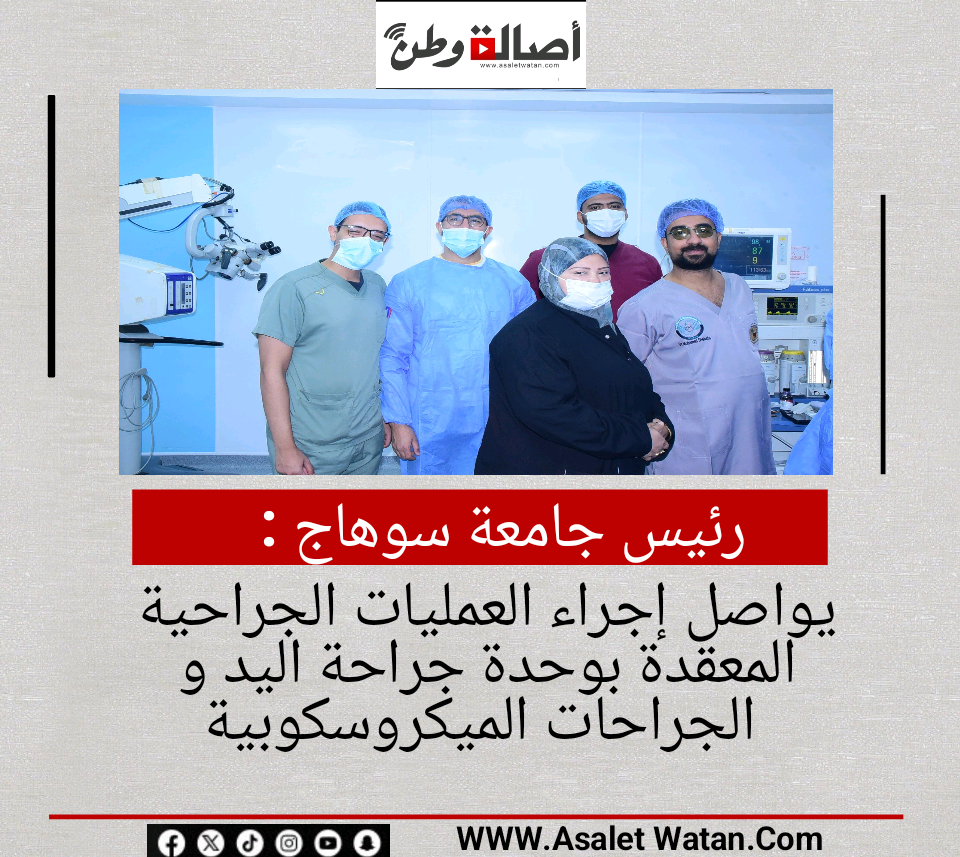

رئيس جامعة سوهاج يواصل إجراء العمليات الجراحية المعقدة بوحدة جراحة اليد و الجراحات الميكروسكوبية

يواصل الدكتور حسان النعماني رئيس جامعة سوهاج واستاذ جراحة اليد والجراحات الميكروسكوبية والفريق الطبي المصاحب له إجراء العمليات الجراحية المعقدة لحاله مصابه بتهتك الضفيرة العصبية، اثر حادث سيارة ادي الي شلل تام للطرف العلوي الايسر، حيث تعد هذه العملية انجاز جديد يضاف لنجاحات الوحده في علاج الحالات المعقدة الصعبة ذات المهارة العاليه، والتي تم اجرائها بوحدة جراحة اليد والجراحات الميكروسكوبية بالمستشفى الجامعي القديم.

وقد ضم الفريق الطبي كلا من الدكتور ياسر سرور استاذ مساعد جراحة العظام واستشاري جراحة اليد والجراحات الميكروسكوبية وعد من الهيئة المعاونة الدكتور محمد شحاته، الدكتور مصطفى عبداللاه، الدكتور بسام، الدكتور رفعت والدكتورة مروة مدرس التخدير والعناية المركزة والدكتور حسام مدرس مساعد التخدير.